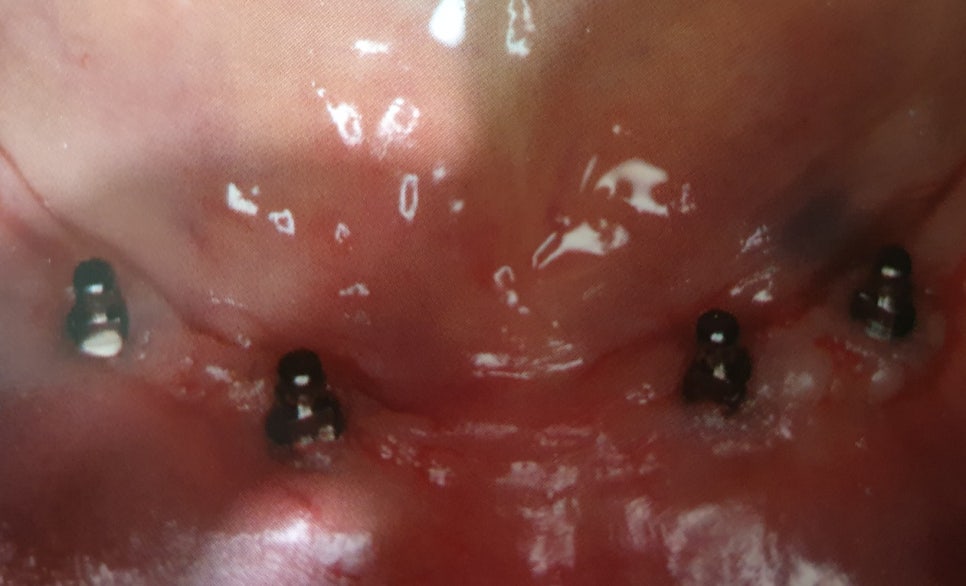

식립한 임플란트가 자신의 잇몸뼈에 잘 유착이 되는데 이때 위의 사진과 같이 단추모양의 어버트먼트를 연결합니다.

치과에서는 보통 2차수술이라고 부릅니다.

아래사진은 실제 2차 수술을 마치고 찍은 사진입니다.